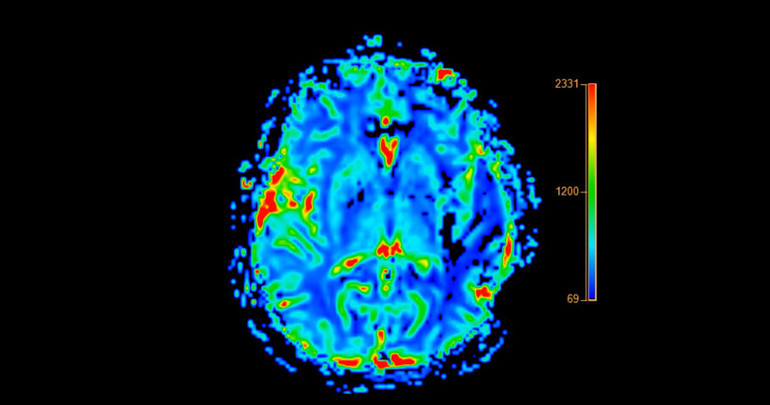

Araştırma ekibi, retinada enfeksiyon belirtileri aradı. Retina, beynin bir uzantısı olarak kabul ediliyor ve eğer bakteriler burada da görülürse, göz testi ile Alzheimer riski taşıyan kişilerin tespit edilmesi mümkün olabilecek.

Sonuçlar, Alzheimer hastalarının retina ve beyinlerinde C. pneumoniae seviyelerinin, normal bilişsel işleve sahip kişilere kıyasla belirgin şekilde yüksek olduğunu ortaya koydu. Bakteriyel yük arttıkça, hastaların ölümden önce gördüğü beyin değişiklikleri ve bilişsel gerileme de daha şiddetliydi.

Araştırmacılar, retina desenlerini bilgisayar analiziyle inceleyerek, göz testlerinin Alzheimer riskini erken aşamada belirleyebileceğini gösterdi. Cedars-Sinai Medical Center’da görevli Prof. Maya Koronyo-Hamaoui, “C. pneumoniae’nin insan dokularında, hücre kültürlerinde ve hayvan modellerinde tutarlı şekilde görülmesi, bakteriyel enfeksiyon, iltihaplanma ve nörodejenerasyon arasında daha önce bilinmeyen bir bağlantıyı ortaya koyuyor” dedi.